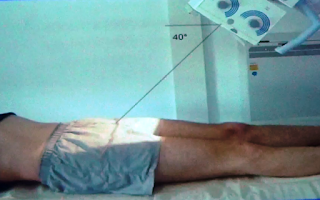

2 DE SALIDA

El rayo central se dirige con una angulación de 40º caudal respecto de la

vertical a la mesa radiológica, se dirige por encima del pubis. En esta

proyección ya no se observan las ramas isquiopubianas ni las iliopubianas. Lo que se observa es el contorno del anillo pelviano para poder

evaluar si existen subluxaciones sacroiliacas.

Cuando este problema se presenta entonces el anillo pelviano se observa asimétrico.